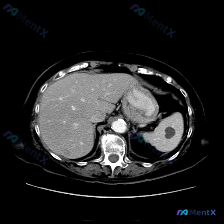

- 基本情况:单幅腹部CT横断面(层面未全,仅看所示范围)

- 脾脏实质内见一类圆形低密度灶,边界尚清晰,内部密度均匀

- 病灶CT值近似水样密度

- 其余肝、胰、双肾、腹膜后在该层面未见明确占位或肿大淋巴结,无腹水

- 关键阴性:周边脂肪间隙清晰,无明显炎性渗出或侵犯征象